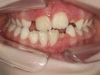

Inversion de l'occlusion des dents antérieures

L'inversion de l'occlusion des dents antérieures, également connue sous le nom d'occlusion croisée antérieure, se produit lorsque les dents inférieures se placent devant les dents supérieures. Cette malocclusion entraîne des problèmes de mastication, et peut induire des usures de l’émail et des problèmes de gencive sur les dents en inversé. Elle peut par ailleurs entraîner une glissement vers l’avant ou le côté de la mâchoire inférieure et en modifier la croissance.

Pourquoi traiter ?

Un traitement précoce permet de rétablir des contacts incisifs et une mastication efficaces, de protéger les dents et leur gencive, et de recentrer la mâchoire du bas si elle est contrainte par la malocclusion.